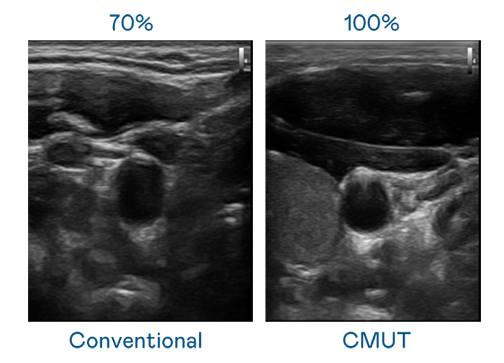

CMUT 技術是一種用電容式微機電元件來產生超音波訊號的技術。與傳統 PZT 壓電式技術相比,CMUT 頻寬增加 30%,更寬頻的超音波訊號讓影像解析度大幅提升,是實現高影像品質醫療超音波掃描、促進精準醫療發展的關鍵技術。

超音波影像的解析度高低,首先取決於探頭能發出的訊號頻寬。爱游戏官网 CMUT 可提供高清晰的超音波訊號,提供高頻寬、高靈敏度、影像紋理細節更高的超音波影像,協助醫護人員縮短影像判讀時間及利用精準的醫療影像進行診斷。